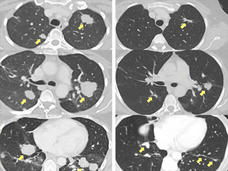

Uso de la expresión génica para diagnosticar de forma más precisa el cáncer de pulmón

Un patrón de expresión génica en las células de las vías respiratorias altas de pacientes con sospecha de cáncer de pulmón puede ayudar a diagnosticar el cáncer de pulmón de forma más precisa que la broncoscopia sola.